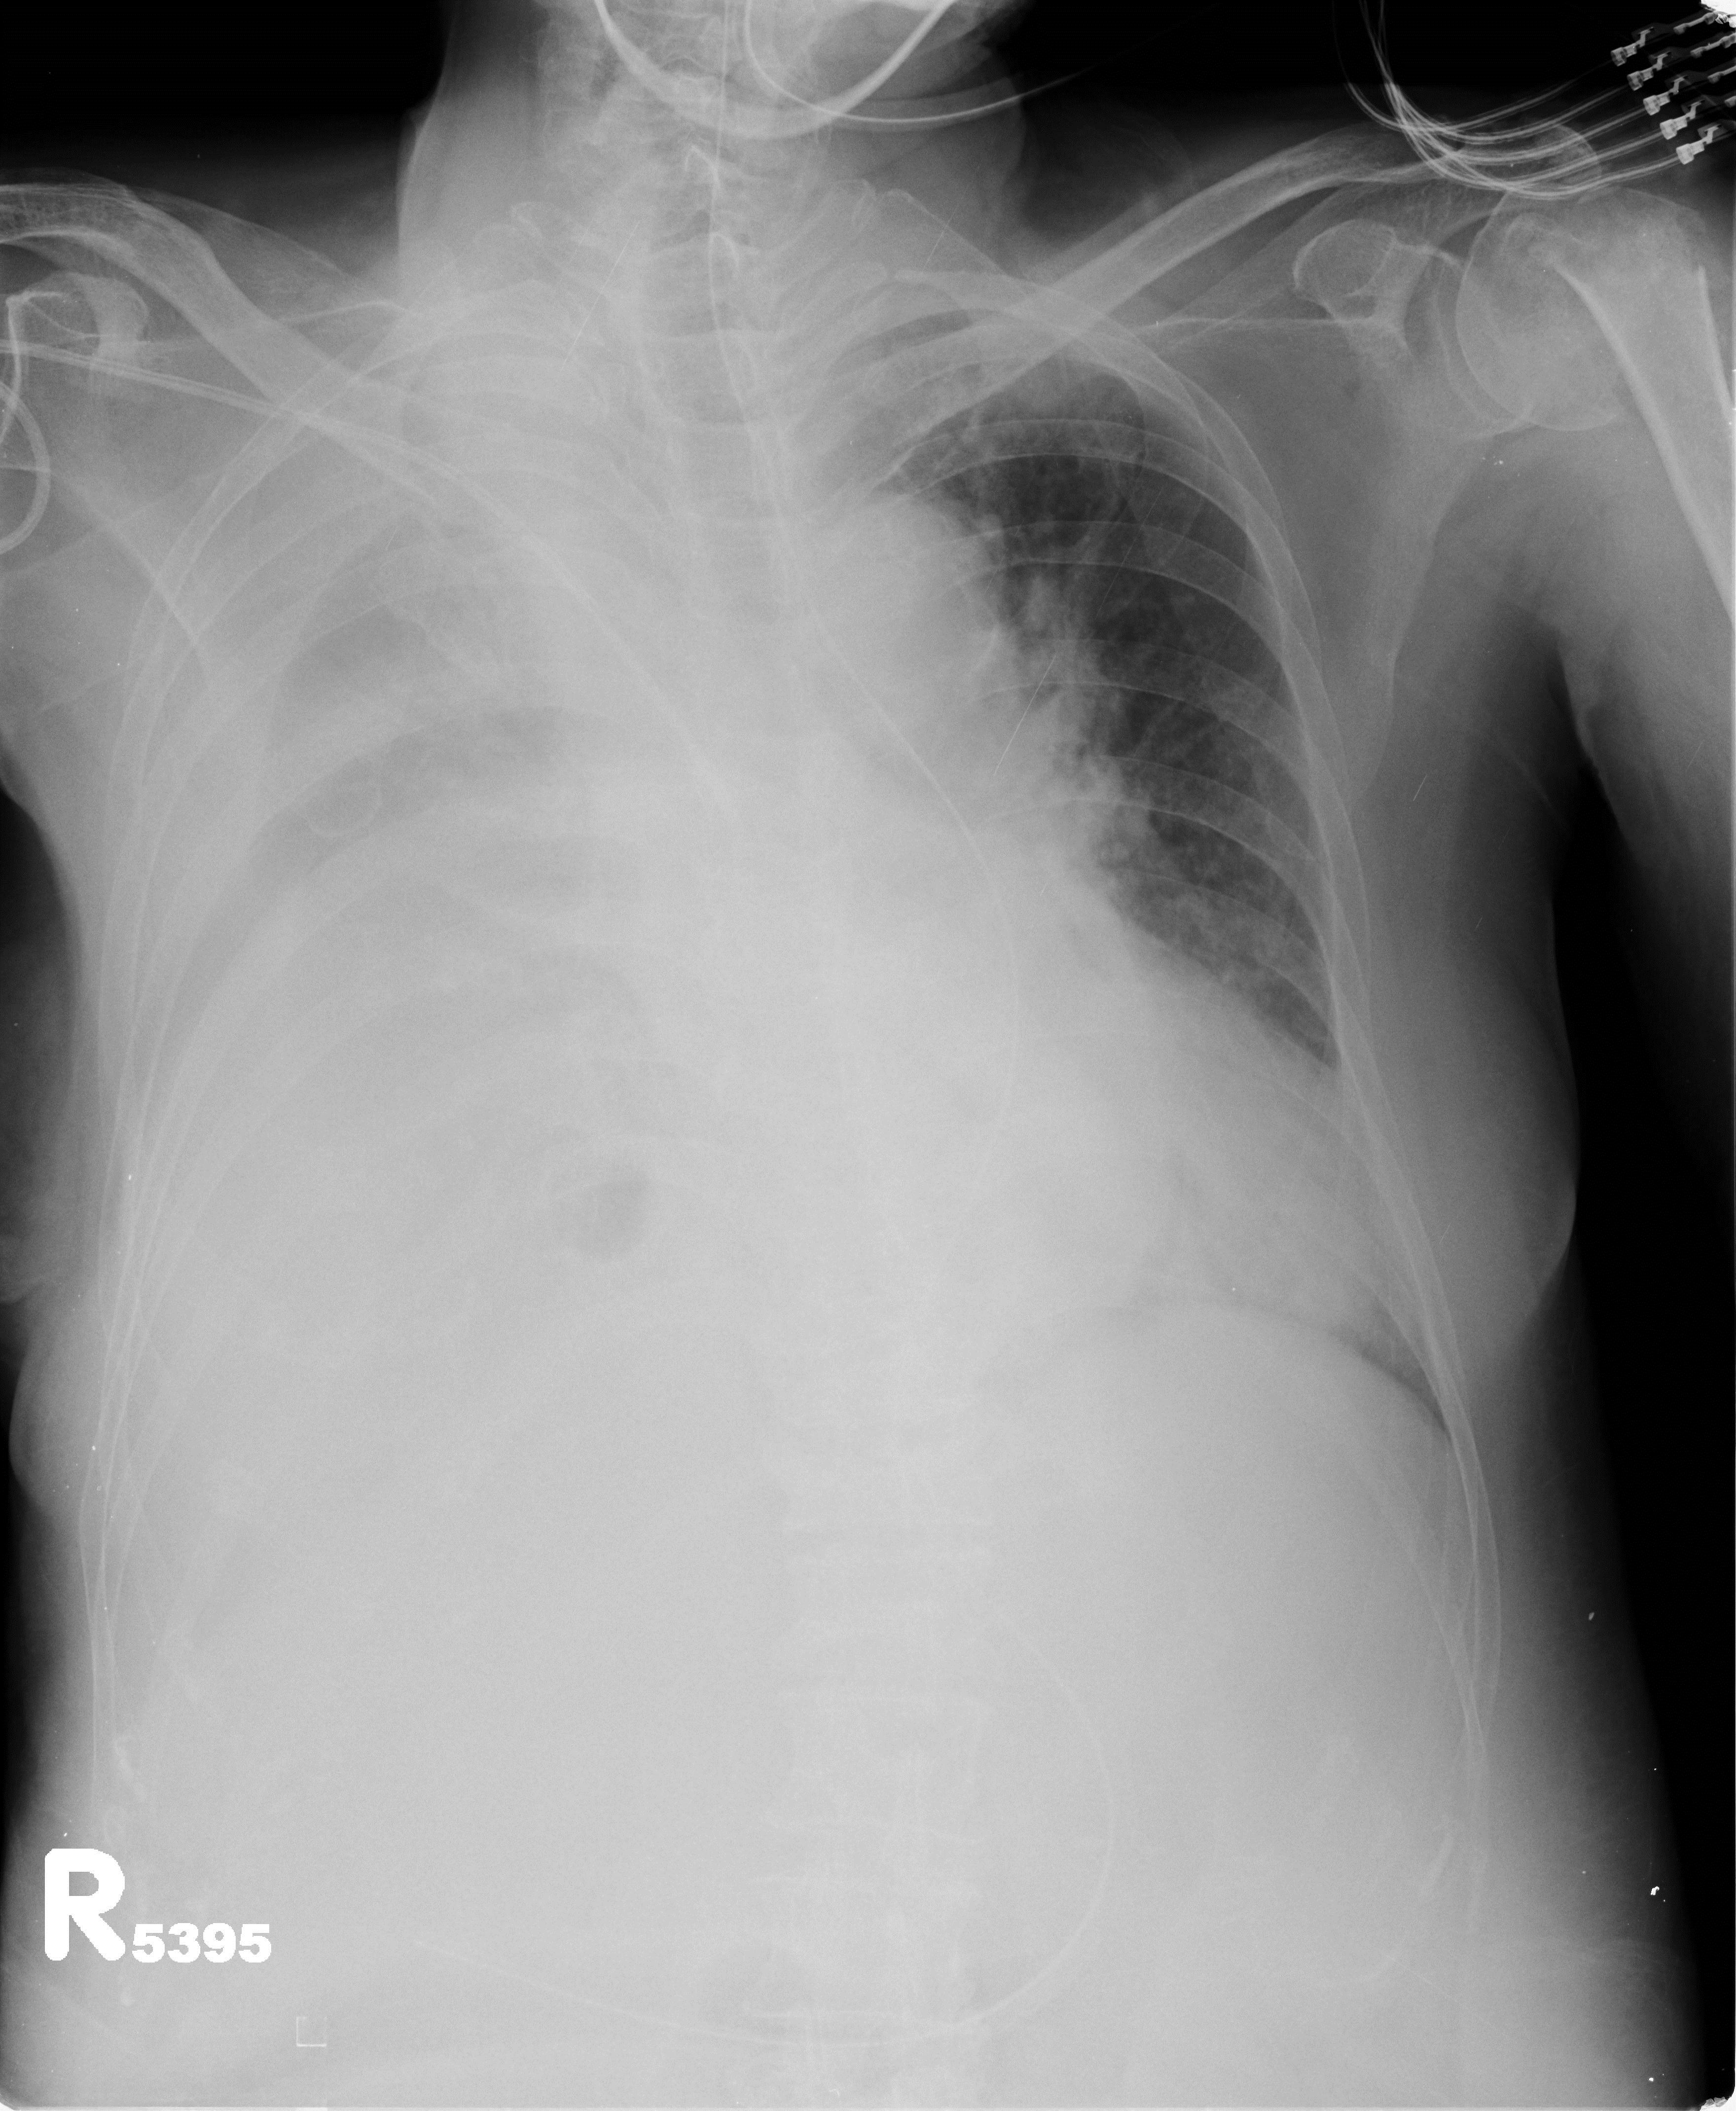

The current treatment algorithm, which often starts as several weeks of outpatient antibiotics, (usually initiated for treatment of community acquired pneumonia that develops into a parapneumonic effusion), that engenders an even longer period after subsequent follow up chest x-rays, then CT scan fail to show improvement.

A pneumonia in late September, becomes an effusion in October, then progresses to empyema as various strategies are attempted and fail.  One antibiotic is switched to another, a pigtail is placed in radiology (with partial results), then perhaps, a larger tube, and fibrinolytics.  Then, only then – is the thoracic surgery service consulted.